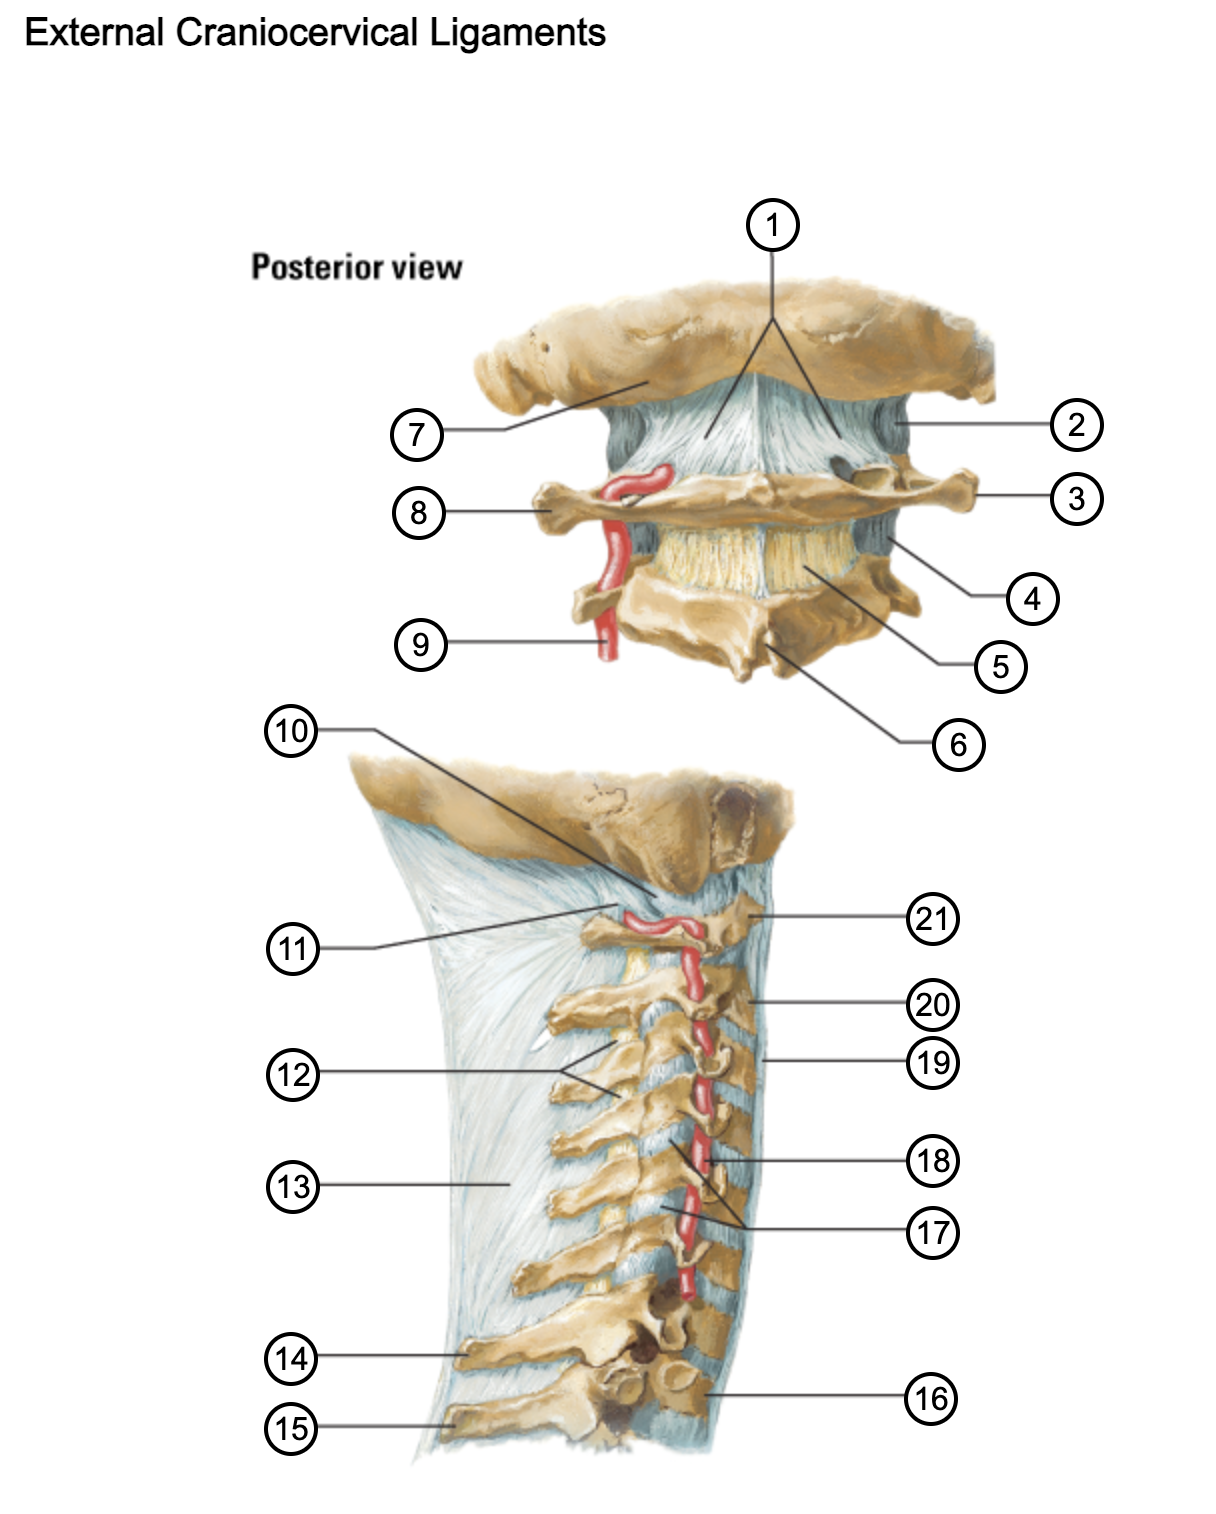

1

posterior antlantooccipital membrane

2

capsule of atlantooccipital joint

3

transverse process of atlas (C1)

4

capsule of lateral atlantoaxial joint

5

ligamenta flava

6

spinous process

7

occipital bone

8

transverse process of atlas (C1)

9

vertebral artery

10

capsule of atlantooccipital membrane

11

posterior atlantooccipital membrane

12

ligamenta flava

13

nuchal ligament

14

spinous process of C7 vertebra

15

spinous process of T1 vertebra

16

T1 vertebra

17

zygapophysical joints (C4-5 and C5-6)

18

vertebral artery

19

anterior longitudinal ligament

20

body of axis

21

Atlas (C1)